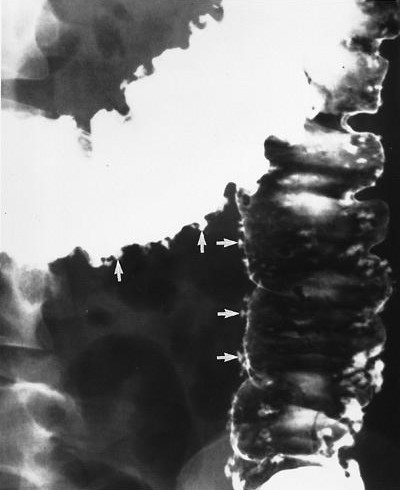

Viêm đại tràng do lao có hình ảnh giống bệnh Crohn, bệnh hiếm ở người da trắng nhưng hay gặp ở người châu Á và bệnh nhân AIDS. Mặc dù phần lớn là thứ phát sau lao phổi, nhưng đa số bệnh nhân không có bằng chứng lao phổi trước đó hoặc lao phổi hoạt động. Với bệnh nhân châu Á, phần lớn bệnh nhân lao ống tiêu hóa là do nuốt trực khuẩn lao bò. Chẩn đoán trực khuẩn kháng axit hoặc u hạt hoại tử bã đậu có độ nhạy thấp (khoảng 32% và 50%, tương ứng) [9]. Với sự hiểu biết tốt hơn về các đặc điểm của viêm lao đại tràng, chẩn đoán sớm bằng chụp cản quang kép là có thể [10]. Các đặc điểm sớm của lao đại tràng là co thắt, tăng tiết, tăng nhu động, tăng sản lympho, các nếp dầy, và các vết loét nông (Hình 18). Các dấu hiệu của viêm lao đại tràng tiến triển khi chụp cản quang kép bao gồm các vết loét ngang (Hình 19), các nốt, các nếp dầy, polyp viêm hoặc sau viêm, hẹp và biến dạng vùng hồi-manh tràng (Hình 20).

Hình 19. Bệnh nhân nữ 22 tuổi bị lao đại tràng giai đoạn tiến triển. Chụp cản quang kép bộc lộ các vết loét ngang và vết loét theo chu vi (mũi tên) ở vùng hồi-manh tràng và đại tràng lên.